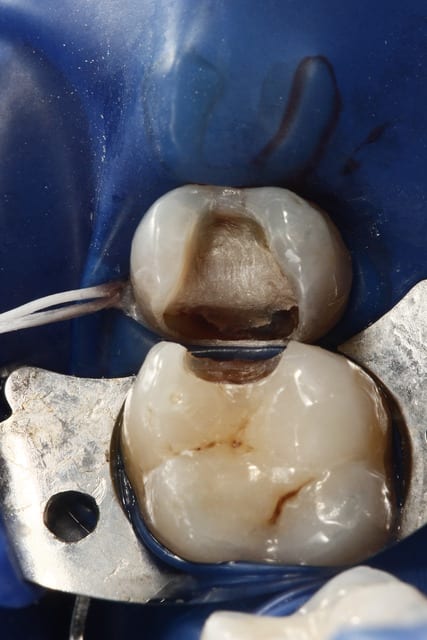

la radio et la photo a 1 mois

Ben les photos finales c'est après réglage de l'occlusion sinon c'est pas drôle.

Quand on s'appuie sur les cuspides restantes et qu'on donne une morphologie assez naturelle, en général il y a peu de retouche occlusale.

Sinon je fais les sillons secondaire a la sonde.

C'est du compo Enamel HRI en dentine et Esthelite en email qui se sculpte facilement et reste pourtant souple et autolissant...

Le polissage c'est des brossettes chargées en silice, et avec de la pâte à polir.